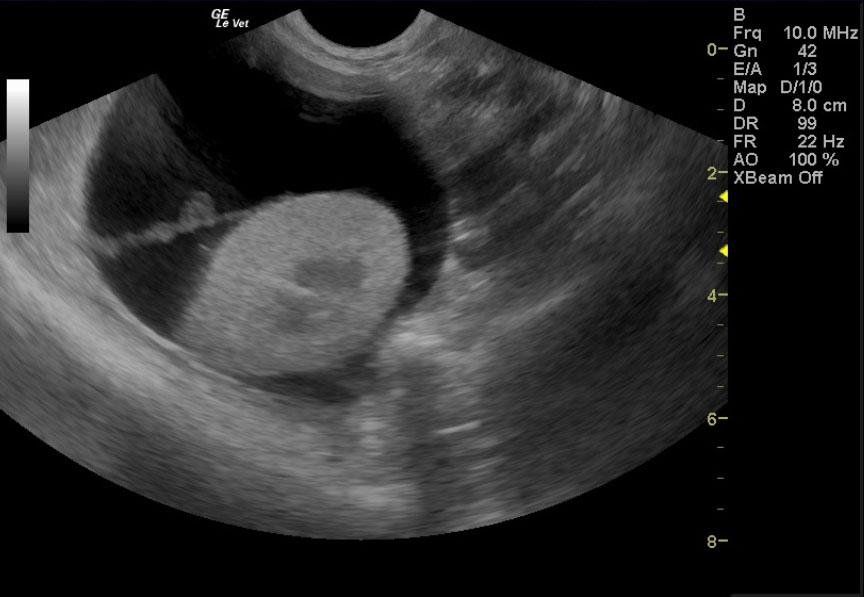

Image Interpretation

Deep right liver mass impinging upon the diaphragm and vena cava dorsally; the mass is likely not resectable. This is probably a cystadenoma, but adenocarcinoma is possible. A right perirenal cyst with a concurrent renal cortical cyst is noted in the right kidney. There is significant renal dystrophy of both kidneys, with pyelectasia or potential concurrent urinary tract infection.